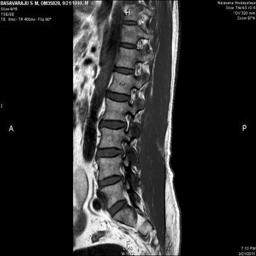

The developed algorithm presented in the previous section was coded using Matlab Version 8.0. The experiment was conducted by considering poor quality spinal cord images of having various lesions. The first column of Fig. 4 shows the axial view of neck spinal cord images of size pixels, respectively. The second column of Fig. 4 presents the same images enhanced using histogram equalization. As is evident from the results presented, the histogram equalization method performs global image enhancement operation which improves the contrast of an image but at the cost loss in image details. The third column of Fig. 4 shows the MSR based spinal cord image enhancement. It can be seen that from the result presented, MSR scheme improves the details that are not clearly visible in histogram equalization technique. In general, image enhancement achieved by MSR method is better compared to histogram equalization. However, the MSR method voilates gray world assumption. Therefore, the image enhanced by this scheme appears to be grayish. Although, numerous work have been reported for solving the problem due to gray world voilation, no work seems to developed for complete elimination.

The fourth column of Fig. 4 shows the image enhanced using Chao et al. []. It can be seen from the results presented that the reconstructed images of Chao’s method have black spots. The appearance of these dark patches degrades the visual quality of the enhanced image. The image enhanced using proposed multirate multiscale retinex image enhancement method presented in the fifth column of Fig. 4, overcomes the drawback of the Chao’s method. As we can see from the simulation results, image enhancement achieved by the proposed method has improved details with significant contrast enhancement. The enhanced images from the proposed method provides information to physicians, radiologists and researchers for various types of pathology detection.